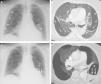

A) Radiografía de tórax en la que se observan múltiples formaciones quísticas subpleurales (asteriscos), en ambos pulmones. B) Imagen axial de la TC de tórax (ventana de pulmón) en la que se visualizan múltiples lesiones quísticas confluyentes en la periferia de ambos pulmones. Nótese la presencia de pequeños vasos pulmonares (flechas) que atraviesan las formaciones quísticas. C) Radiografía de tórax en la que se identifica la aparición de un nivel hidroaéreo (flechas) en una lesión quística de la base pulmonar izquierda (asterisco). D) Reconstrucción axial proyección de mínima intensidad (minIP), en la que se aprecia el nivel hidroaéreo (flechas) correspondiente al sangrado en el interior de una lesión quística (asterisco) del lóbulo inferior izquierdo.

Presentamos el caso de una hemorragia intraquística pulmonar secundaria a anticoagulación en una paciente no fumadora de 59 años con afectación pulmonar quística grave asociada a una EDCL. La paciente consultó por disnea progresiva y dolor torácico, y entre sus antecedentes personales destacaban, además de la enfermedad pulmonar quística secundaria a EDCL (para la que se encuentra en lista de espera para un trasplante pulmonar), un mieloma múltiple diagnosticado 8 años antes y un síndrome nefrótico refractario a tratamiento esteroideo secundario a la EDCL. Una radiografía de tórax (fig. 1A) demostró múltiples imágenes quísticas en ambos pulmones de predominio subpleural (ya conocidas). Una angiotomografía computarizada (angio-TC) de tórax detectó un tromboembolismo pulmonar (TEP), además de la presencia de grandes lesiones quísticas subpleurales de paredes finas en todos los lóbulos (descritas en estudios previos) atravesadas de vasos pulmonares (fig. 1B). Cuatro semanas después del inicio del tratamiento anticoagulante, la paciente presentó un episodio de dolor torácico izquierdo y un esputo hemoptoico, detectándose en la radiografía de tórax la aparición de un nivel hidroaéreo en la base pulmonar izquierda (fig. 1C). Una tomografía computarizada (TC) de tórax confirmó la presencia de un nivel hidroaéreo en el interior de una lesión quística del lóbulo inferior izquierdo (fig. 1D). La densidad elevada del componente líquido intracavitario sugería un sangrado reciente. Se procedió a embolizar con partículas de gelfoam las ramas arteriales pulmonares que rodeaban la formación quística sangrada, mejorando la sintomatología de la paciente.